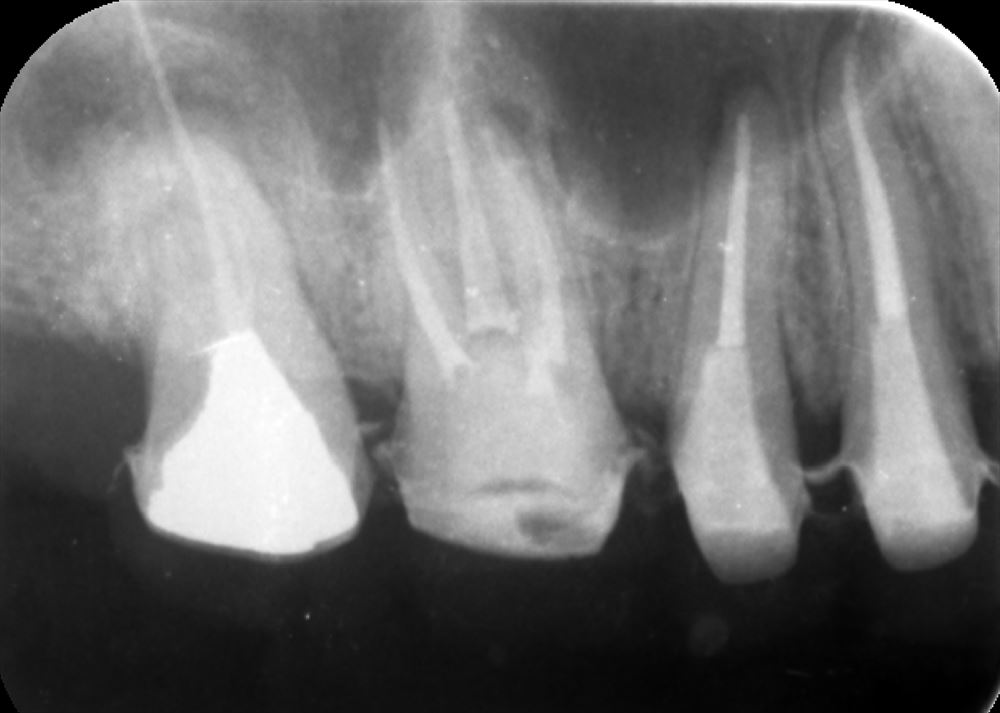

上顎6番が治らない方の2回目

先日MB2を発見し

今日は2回目で仕上げ

こういう所の感染源を取り残さない。

レーザー

根管充填

症状もなく患者さま喜んで頂けました。抜く必要はありません。